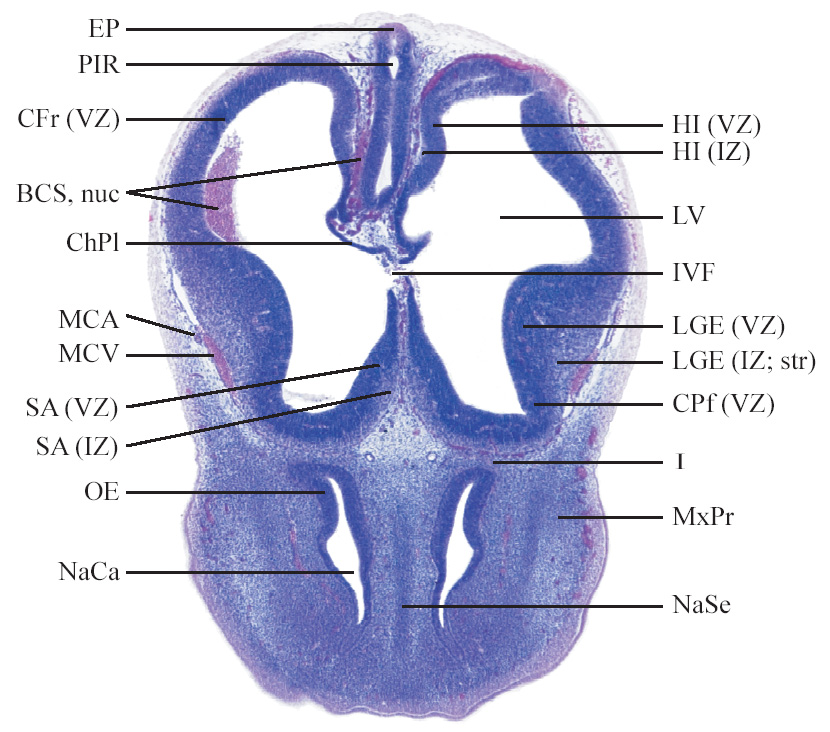

C57BL/6J GD12 Mouse Brain Atlas

Slides from U. Schambra, coronal cuts with slides at every 5th section, with a hematoxylin and eosin (H & E) stain

Currently on section 55.